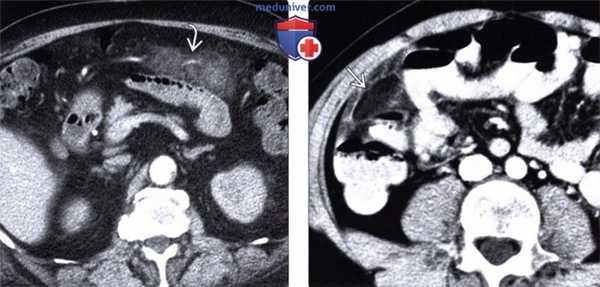

3. КТ при сегментарном инфаркте сальника:

• КТ с контрастным усилением:

о Измененная жировая клетчатка локализуется между прямыми мышцами живота и ободочной кишкой

- Может выявляться очаговое затенение жировой клетчатки или, чаще, крупное (>5 см) неконтрастируемое гетерогенное образование сальника в сочетании с исчерченностью жировой клетчатки

о Может наблюдаться симптом центральной точки (центральный очаг с высоким коэффициентом ослабления, представляющий собой центральный застойный или тромбированный сосуд/кровоизлияние)

о Соседние ободочная кишка, желчный пузырь и червеобразный отросток не изменены

о Реже наблюдается скопление свободной жидкости и минимальное реактивное утолщение ободочной кишки

(Левый) Пациент с жалобами на острые боли в правой верхней части живота. При УЗИ брюшной полости в верхнем правом квадранте живота под передней брюшной стенкой определяется эхогенное эллипсоидное образование. Прилегающий желчный пузырь выглядит не измененным (не показан).

(Правый) У этого же пациента при КТ с контрастным усилением на аксиальной томограмме в правом верхнем квадранте живота определяется затенение жировой клетчатки сальника, что соответствует изменениям, выявленным при УЗИ. Обратите внимание на отсутствие видимых изменений прилегающего тонкостенного желчного пузыря.